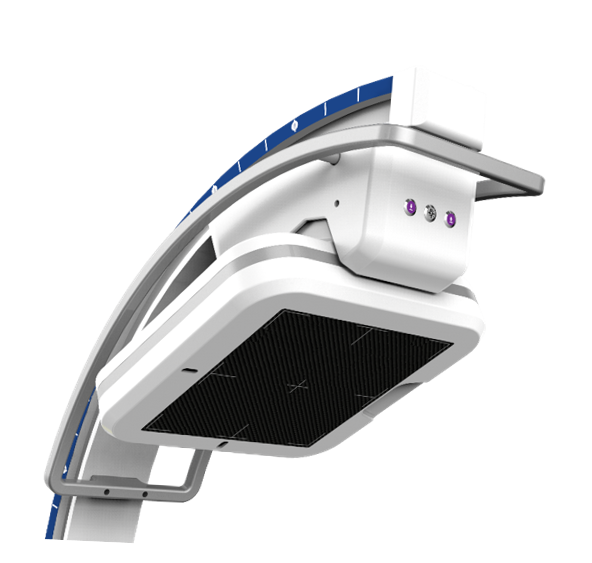

在C臂扫描过程中,始终保持拍摄主体处于射线束的中心,避免了序列图像采集过程中的横纵方向运动,减少相对运动造成的运动伪影。

平板垂直升降运动 便于术中微调平板与拍摄主体的距离,更加贴近病灶体,成像范围更大,图像更清晰。